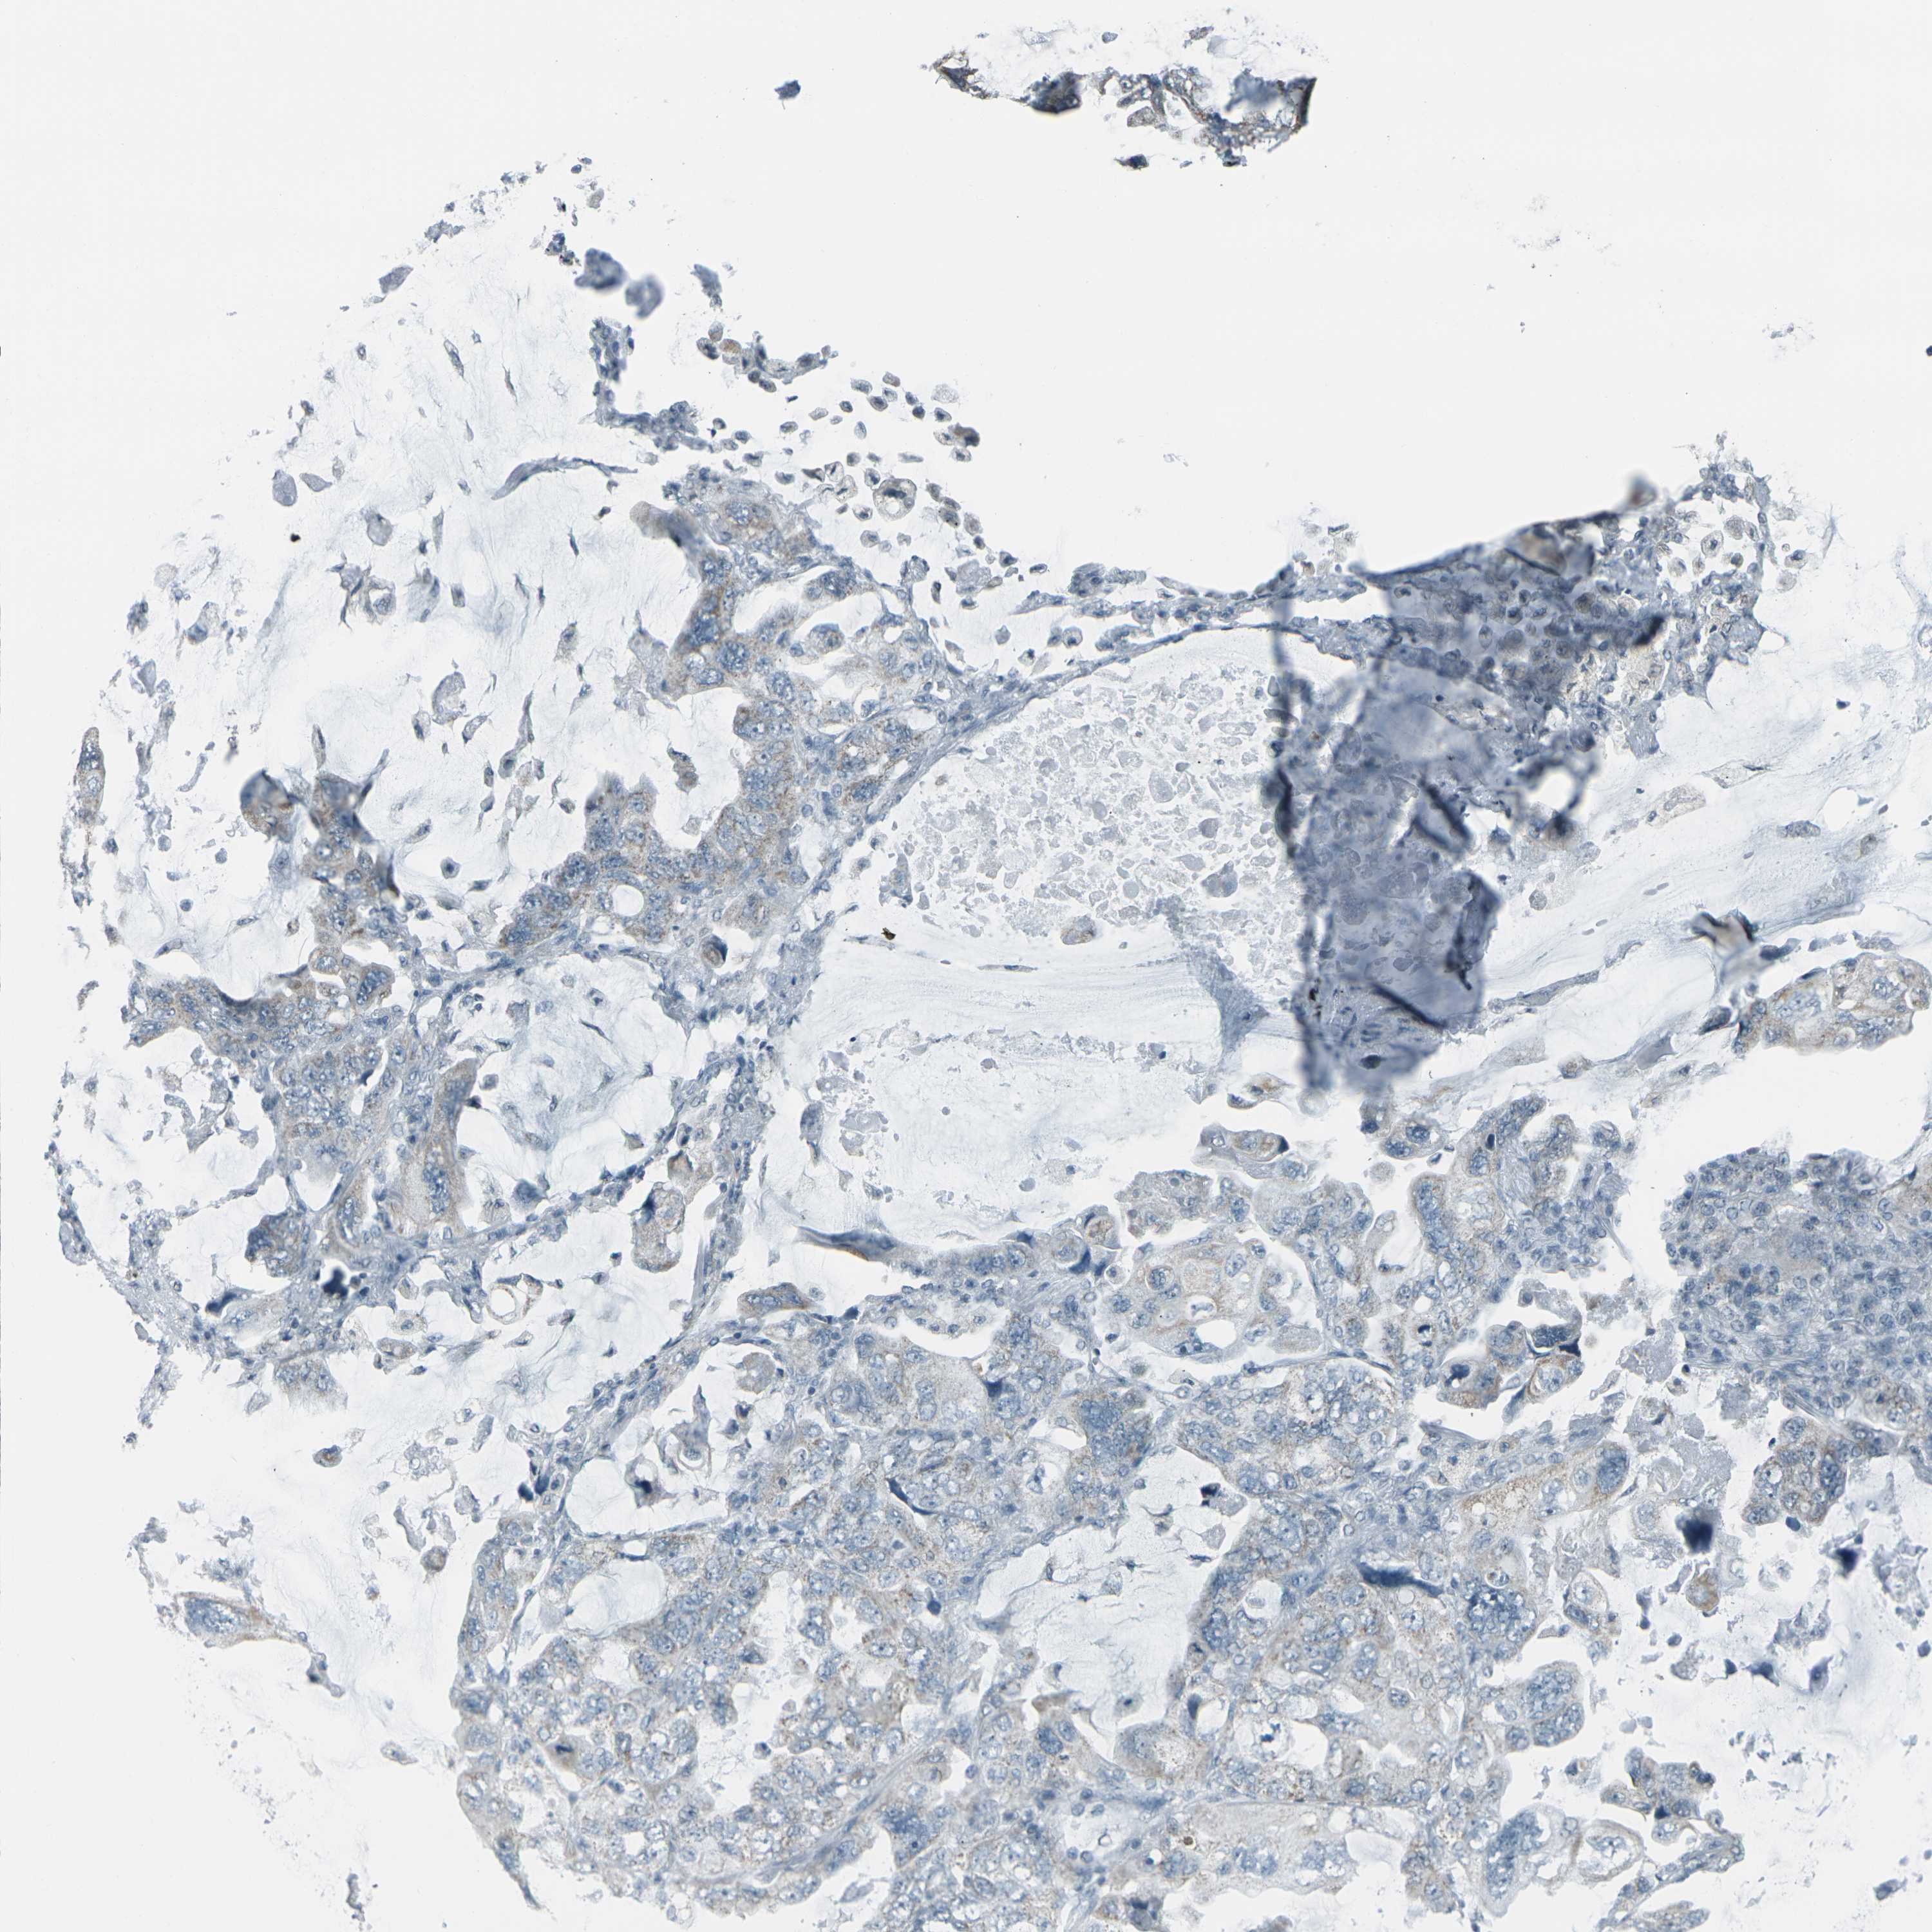

CANCER LUNG CANCER Show tissue menu

Lung cancer

Human cancer